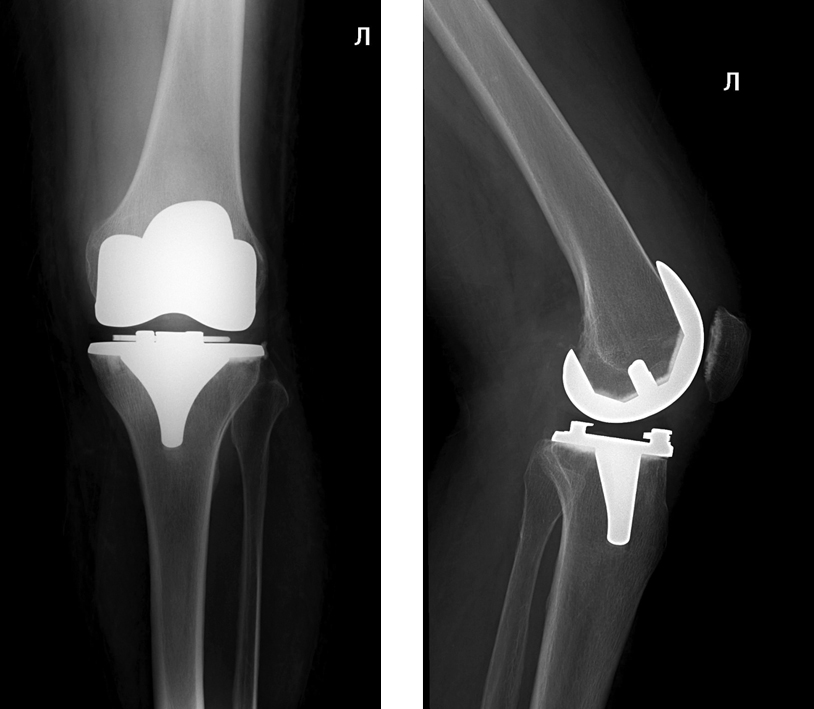

Пациентка 70 лет обратилась в клинику НМИЦ ТО им. Р.Р. Вредена по поводу терминального левостороннего гонартроза с варусной деформацией и комбинированной контрактурой коленного сустава (рис. 1).

Рис. 1. Рентгенограммы коленного сустава пациентки, выполненные при поступлении в клинику

Fig. 1. Knee X-rays performed on admission to the clinic